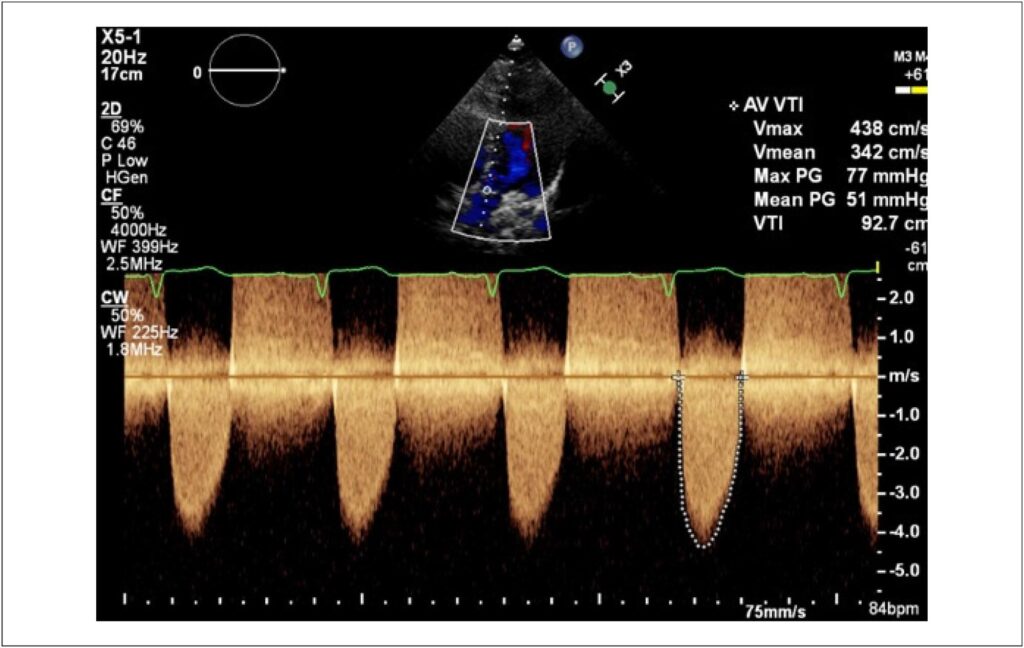

Unicuspid aortic valve (UAV) is an uncommon congenital pathology, first described by Edwards in 1958. It is a rare malformation (especially when compared to other aortic valve anomalies), with an estimated incidence of 0.02% of adults undergoing echocardiography and approximately 4% to 5% of patients undergoing surgery for aortic stenosis. Echocardiography is the first-choice method for diagnosis and definition of hemodynamic repercussions. In this study, we report the case of a patient with symptomatic aortic stenosis and describe her diagnosis and therapeutic management.